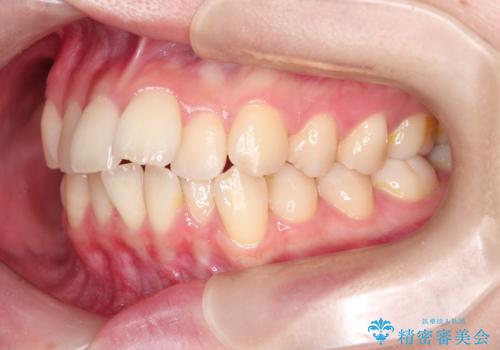

- 前歯のがたがたを主訴に来院されました。

上下の前歯が前方に傾斜しているのもあり、内側に前歯をひっこめるために上下左右の歯を1本ずつ抜歯して矯正することとしました。